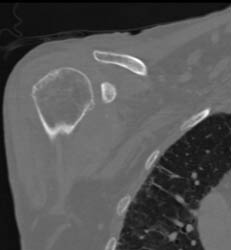

Trauma to Ankle With Fracture and Joint Fragments